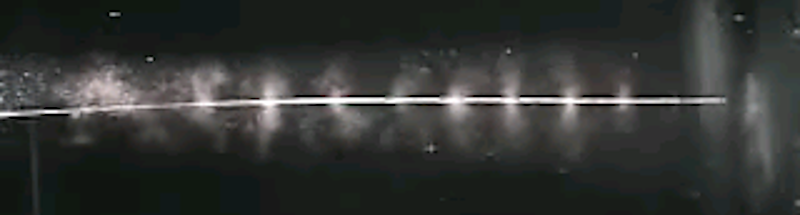

The image below shows the active section of a catheter while the waveguide is undergoing transverse motion.